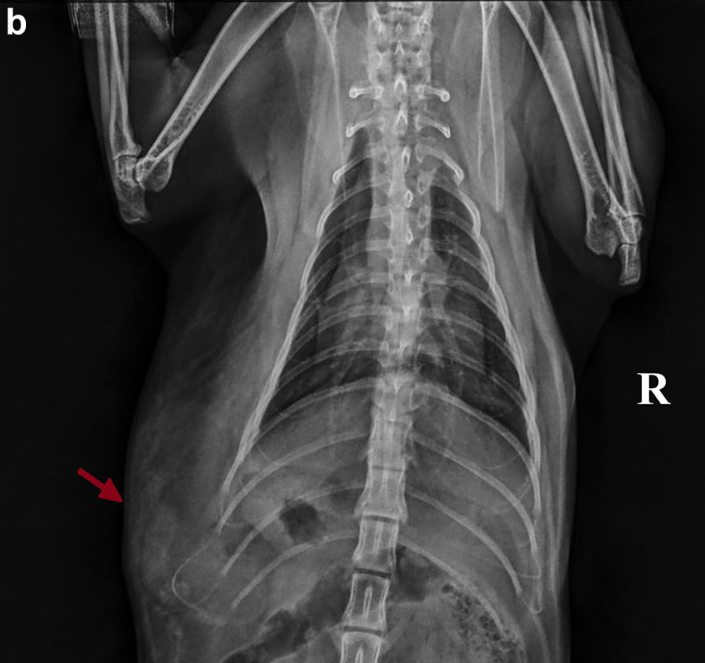

옆구리 탈장(Paracostal hernia)은 복벽의 일부인 외복사근과 복횡근이 갈비뼈나 늑연골 부착부위에서 찢어지면서 복강 내 장기가 피하 공간으로 탈출하는 상태를 말합니다. 주로 교통사고나 다른 동물과의 싸움 등 외상으로 인해 복압이 급격히 상승하면서 발생합니다.

- 결과 1: 횡격막 탈장의 높은 동반율 가장 주목할 만한 결과는 옆구리 탈장이 확인된 고양이 19마리 중 12마리(63%)에서 횡격막 탈장이 함께 발견되었다는 점입니다. 이는 옆구리 탈장 진단 시 횡격막의 상태를 반드시 함께 평가해야 함을 시사합니다.

따라서 옆구리 탈장이 의심되는 외상 환자의 경우, 수술 전 방사선 검사 등 영상 진단을 통해 횡격막의 연속성을 면밀히 평가해야 합니다. 또한, 수술 시에는 탈장 부위에 국소적으로 접근하기보다는 복부 정중선 절개를 통해 복강을 열고, 횡격막 전체를 시각적으로 직접 확인하여 손상 여부를 평가하는 것이 강력히 권장됩니다.